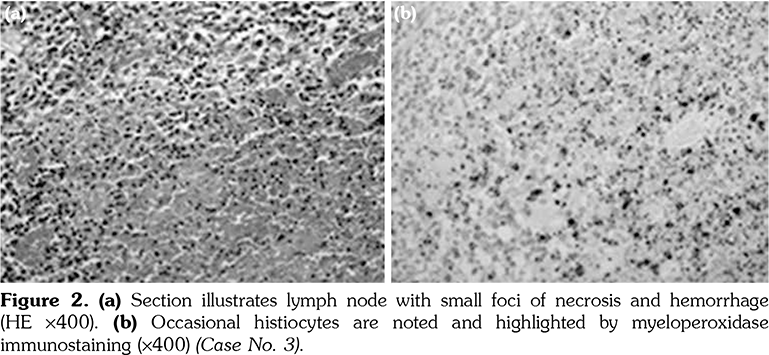

The excised cervical LNs of the 11 patients showed variable degrees of necrotizing lymphadenitis with foci of necrosis surrounded by histiocytes that are positive for CD68 and myeloperoxidase. The histopathology of the excised LN for patients numbered 2, 3, and 7 is illustrated in Figures 1, 2 and 3, respectively.